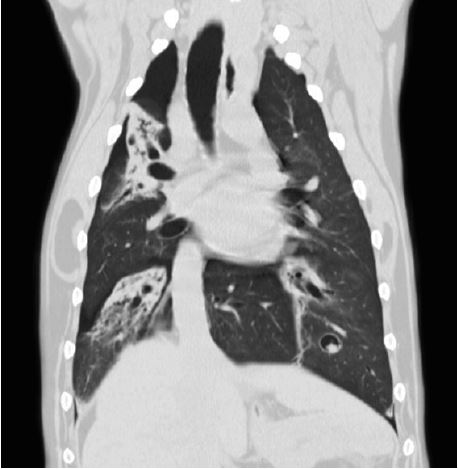

Діафрагмальна грижа

Дихальні шляхи

Чіткі, різкі зображення з високою роздільною здатністю необхідні для встановлення найточнішого діагнозу. А швидке отримання та інтерпретація оптимізує робочий процес і має важливе значення в екстрених ситуаціях. Ви можете досягти високої якості зображення швидше за допомогою багаторядного детектора PUREVision від Aquilion, який має на 40% більшу світловіддачу порівняно з іншими системами. Це єдиний доступний багаторядний детектор з фактичною роздільною здатністю 0,5 мм. Справжня ізотропна роздільна здатність унікального детектора Aquilion PUREVision дозволяє проводити багатоплощинні реконструкції з найвищою просторовою роздільною здатністю у всіх площинах.

Чутлива технологія управління контрастом забезпечує стабільно високу якість результатів для діагностики різних судинних захворювань. Технологія SEMAR (Single Energy Metal Artifact Reduction) від Canon Medical мінімізує артефакти від металу та покращує візуалізацію імплантатів, опорної кістки та прилеглих м'яких тканин. Передові технології Canon Medical для комп'ютерного томографа Aquilion включають методи адаптивного ітеративного зменшення дози 3D (AIDR 3D) та вдосконалену інтелектуальну реконструкцію з глибоким навчання Clear-IQ Engine (AiCE) (DLR). Ця виняткова реконструкція на основі штучного інтелекту значно знижує рівень шуму і підвищує SNR (співвідношення сигналу до шуму).